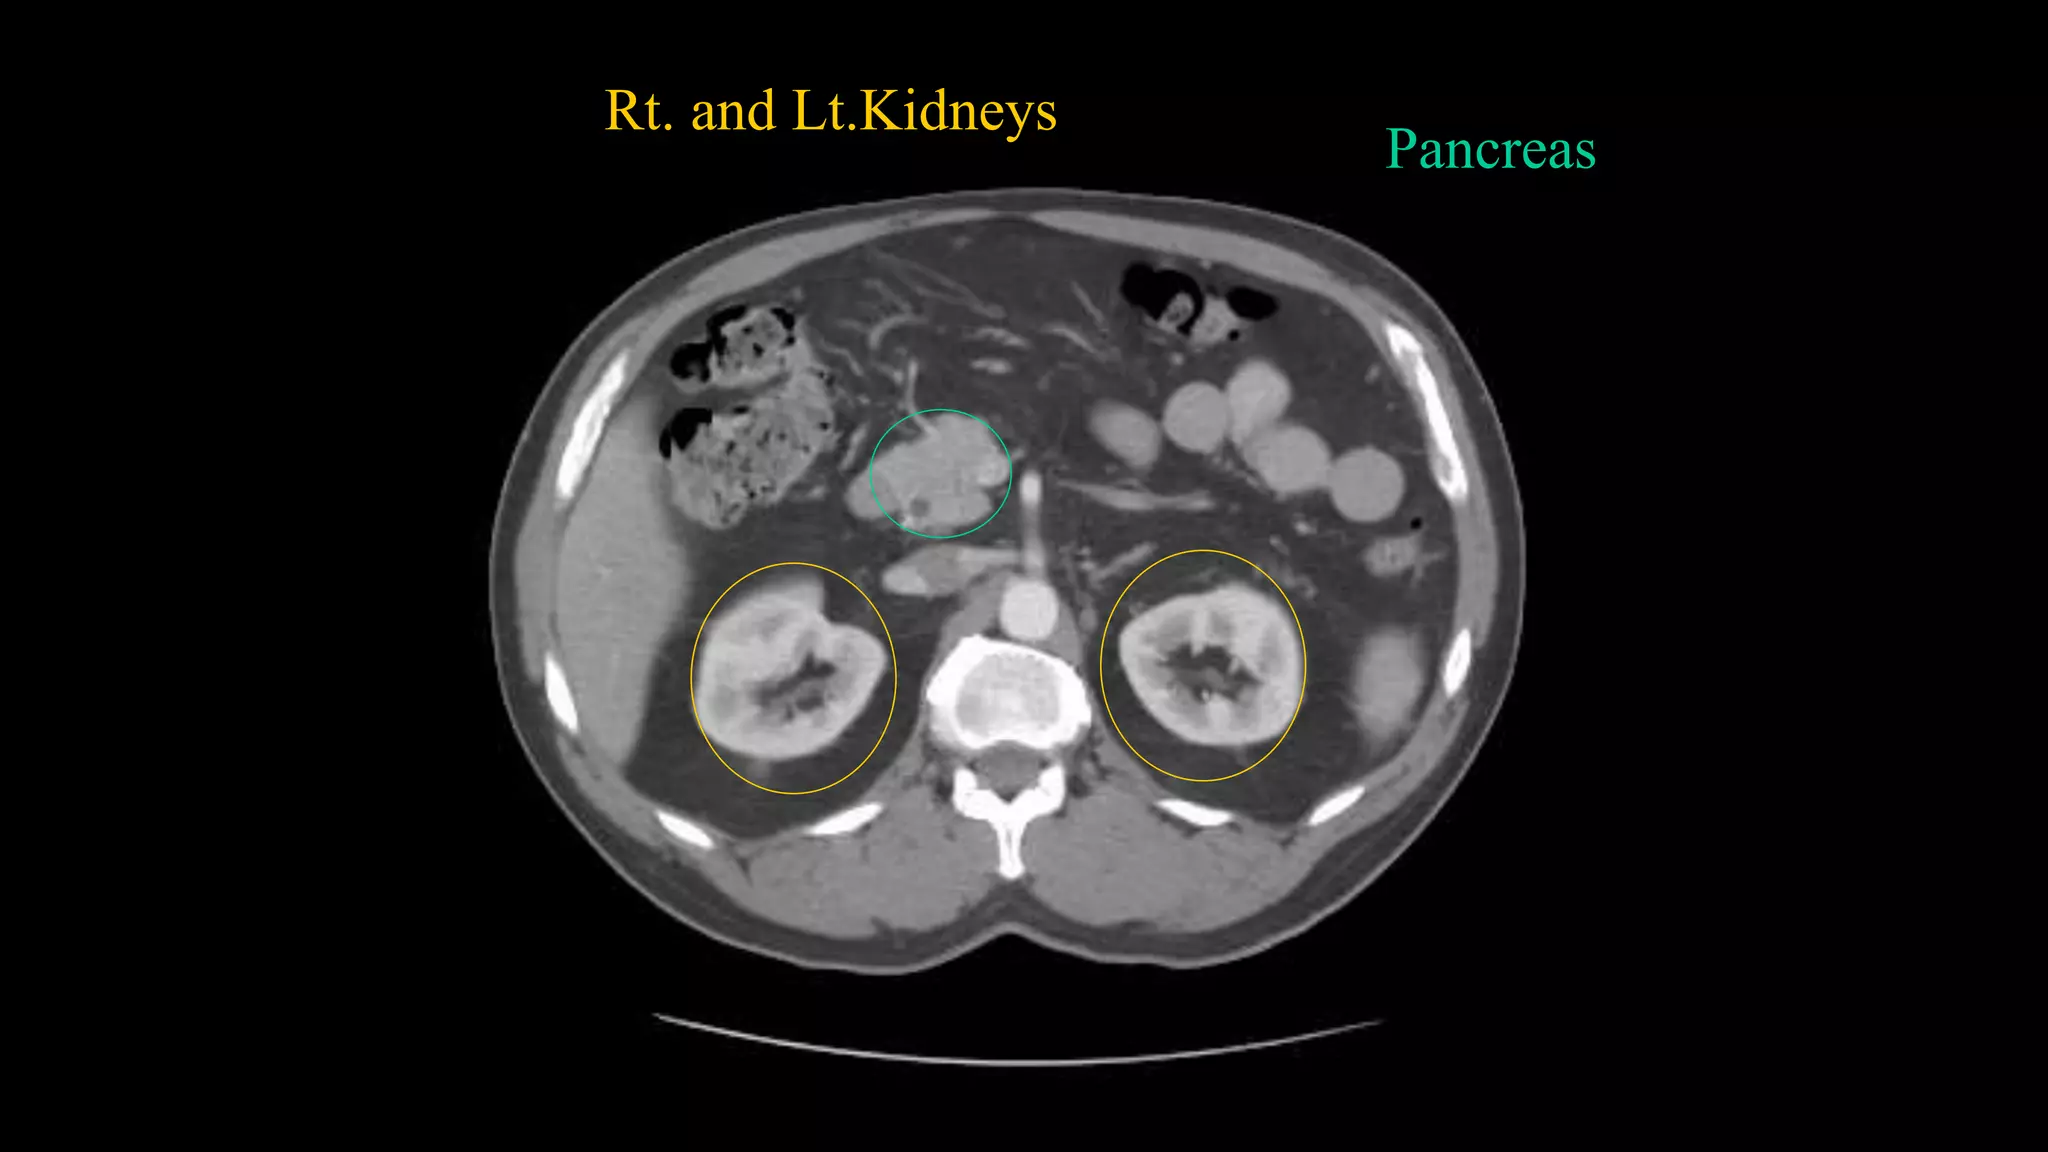

Rt. and Lt.Kidneys

Pancreas